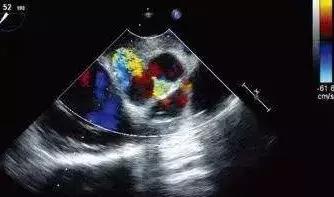

彩超具有彩色多普勒血流显像功能,可以显示病变区域的血管解剖结构、血流方向、血流速度和血流状态改变,可以明显提高对疾病的鉴别能力,提高诊断的准确性。

包括常规超声心动图检查、颈部动静脉、腹腔动静脉、肾动脉、四肢大动脉及深静脉系的形态结构、血流动力学检查。

超声心动图检查系将超声探头置于胸壁、食管内,对立体的心脏进行无数切面扫描、综合分析心脏各结构的位置、形态、活动与血流特点,从而获得心血管疾病的解剖、生理、病理及血流动力学诊断资料。近年来食管内超声进一步拓宽其应用范围,大大提高了诊断敏感性与特异性。

2、心瓣膜病变:对心瓣膜狭窄、关闭不全、瓣叶钙化、脱垂、穿孔、瓣环钙化、赘生物附着、瓣叶发育畸形等病变均能作出明确诊断。